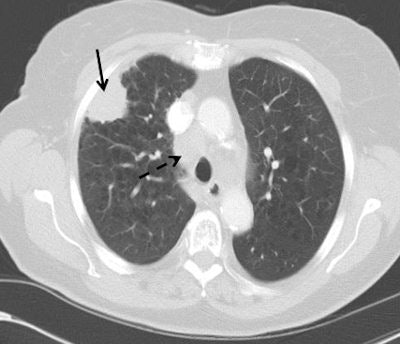

Top: Early stage lung cancer detected by CT. The 10-year survival rate is more than 90%. Bottom: A stage IIIa lung cancer where cure is unlikely. Solid line primary cancer can be seen, and the dotted line shows mediastinal nodes. All images courtesy of Dr. David Baldwin.